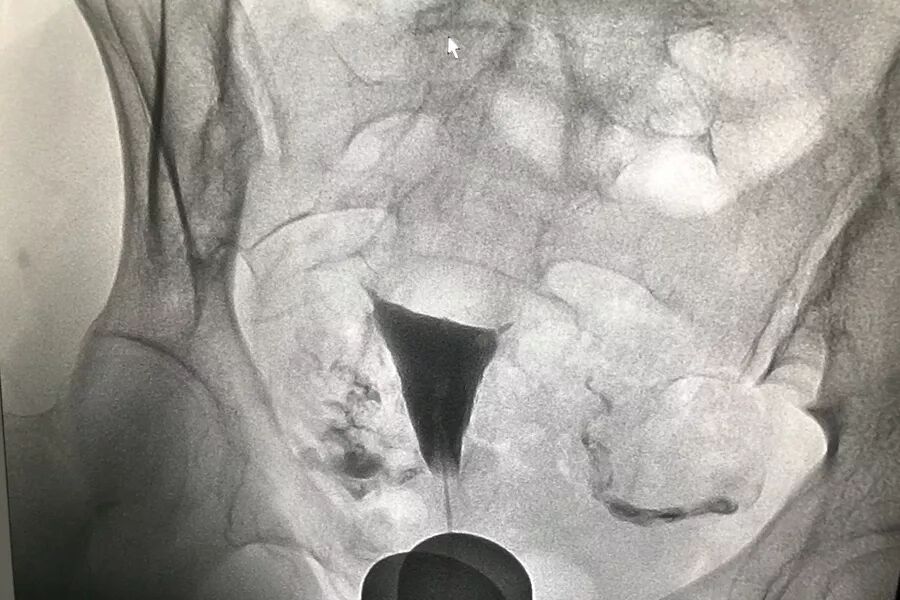

输卵管造影检查,是通过导管向宫腔及输卵管注入造影剂,利用X线摄片,根据造影剂在输卵管及盆腔内的显影情况,来了解输卵管是否通畅、阻塞部位及宫腔形态。能直观地了解输卵管是否通畅以及阻塞的部位,而且能观察子宫腔的大小、形态、有无畸形及有无宫腔粘连或占位性病变。

我院所用的造影剂是碘海醇,属于含碘的水溶性制剂,而并非传统的“碘油”制剂。“碘水”是一个非离子型水溶性造影剂,稳定性更好,毒性更小,不良反应发生率更低。而且我院开展的新技术将DSA应用于子宫输卵管造影,DSA下可持续动态观察子宫及输卵管的显影情况,能提高诊断准确率,避免假阴性,对于不孕症的诊断水平又提升了一个台阶。